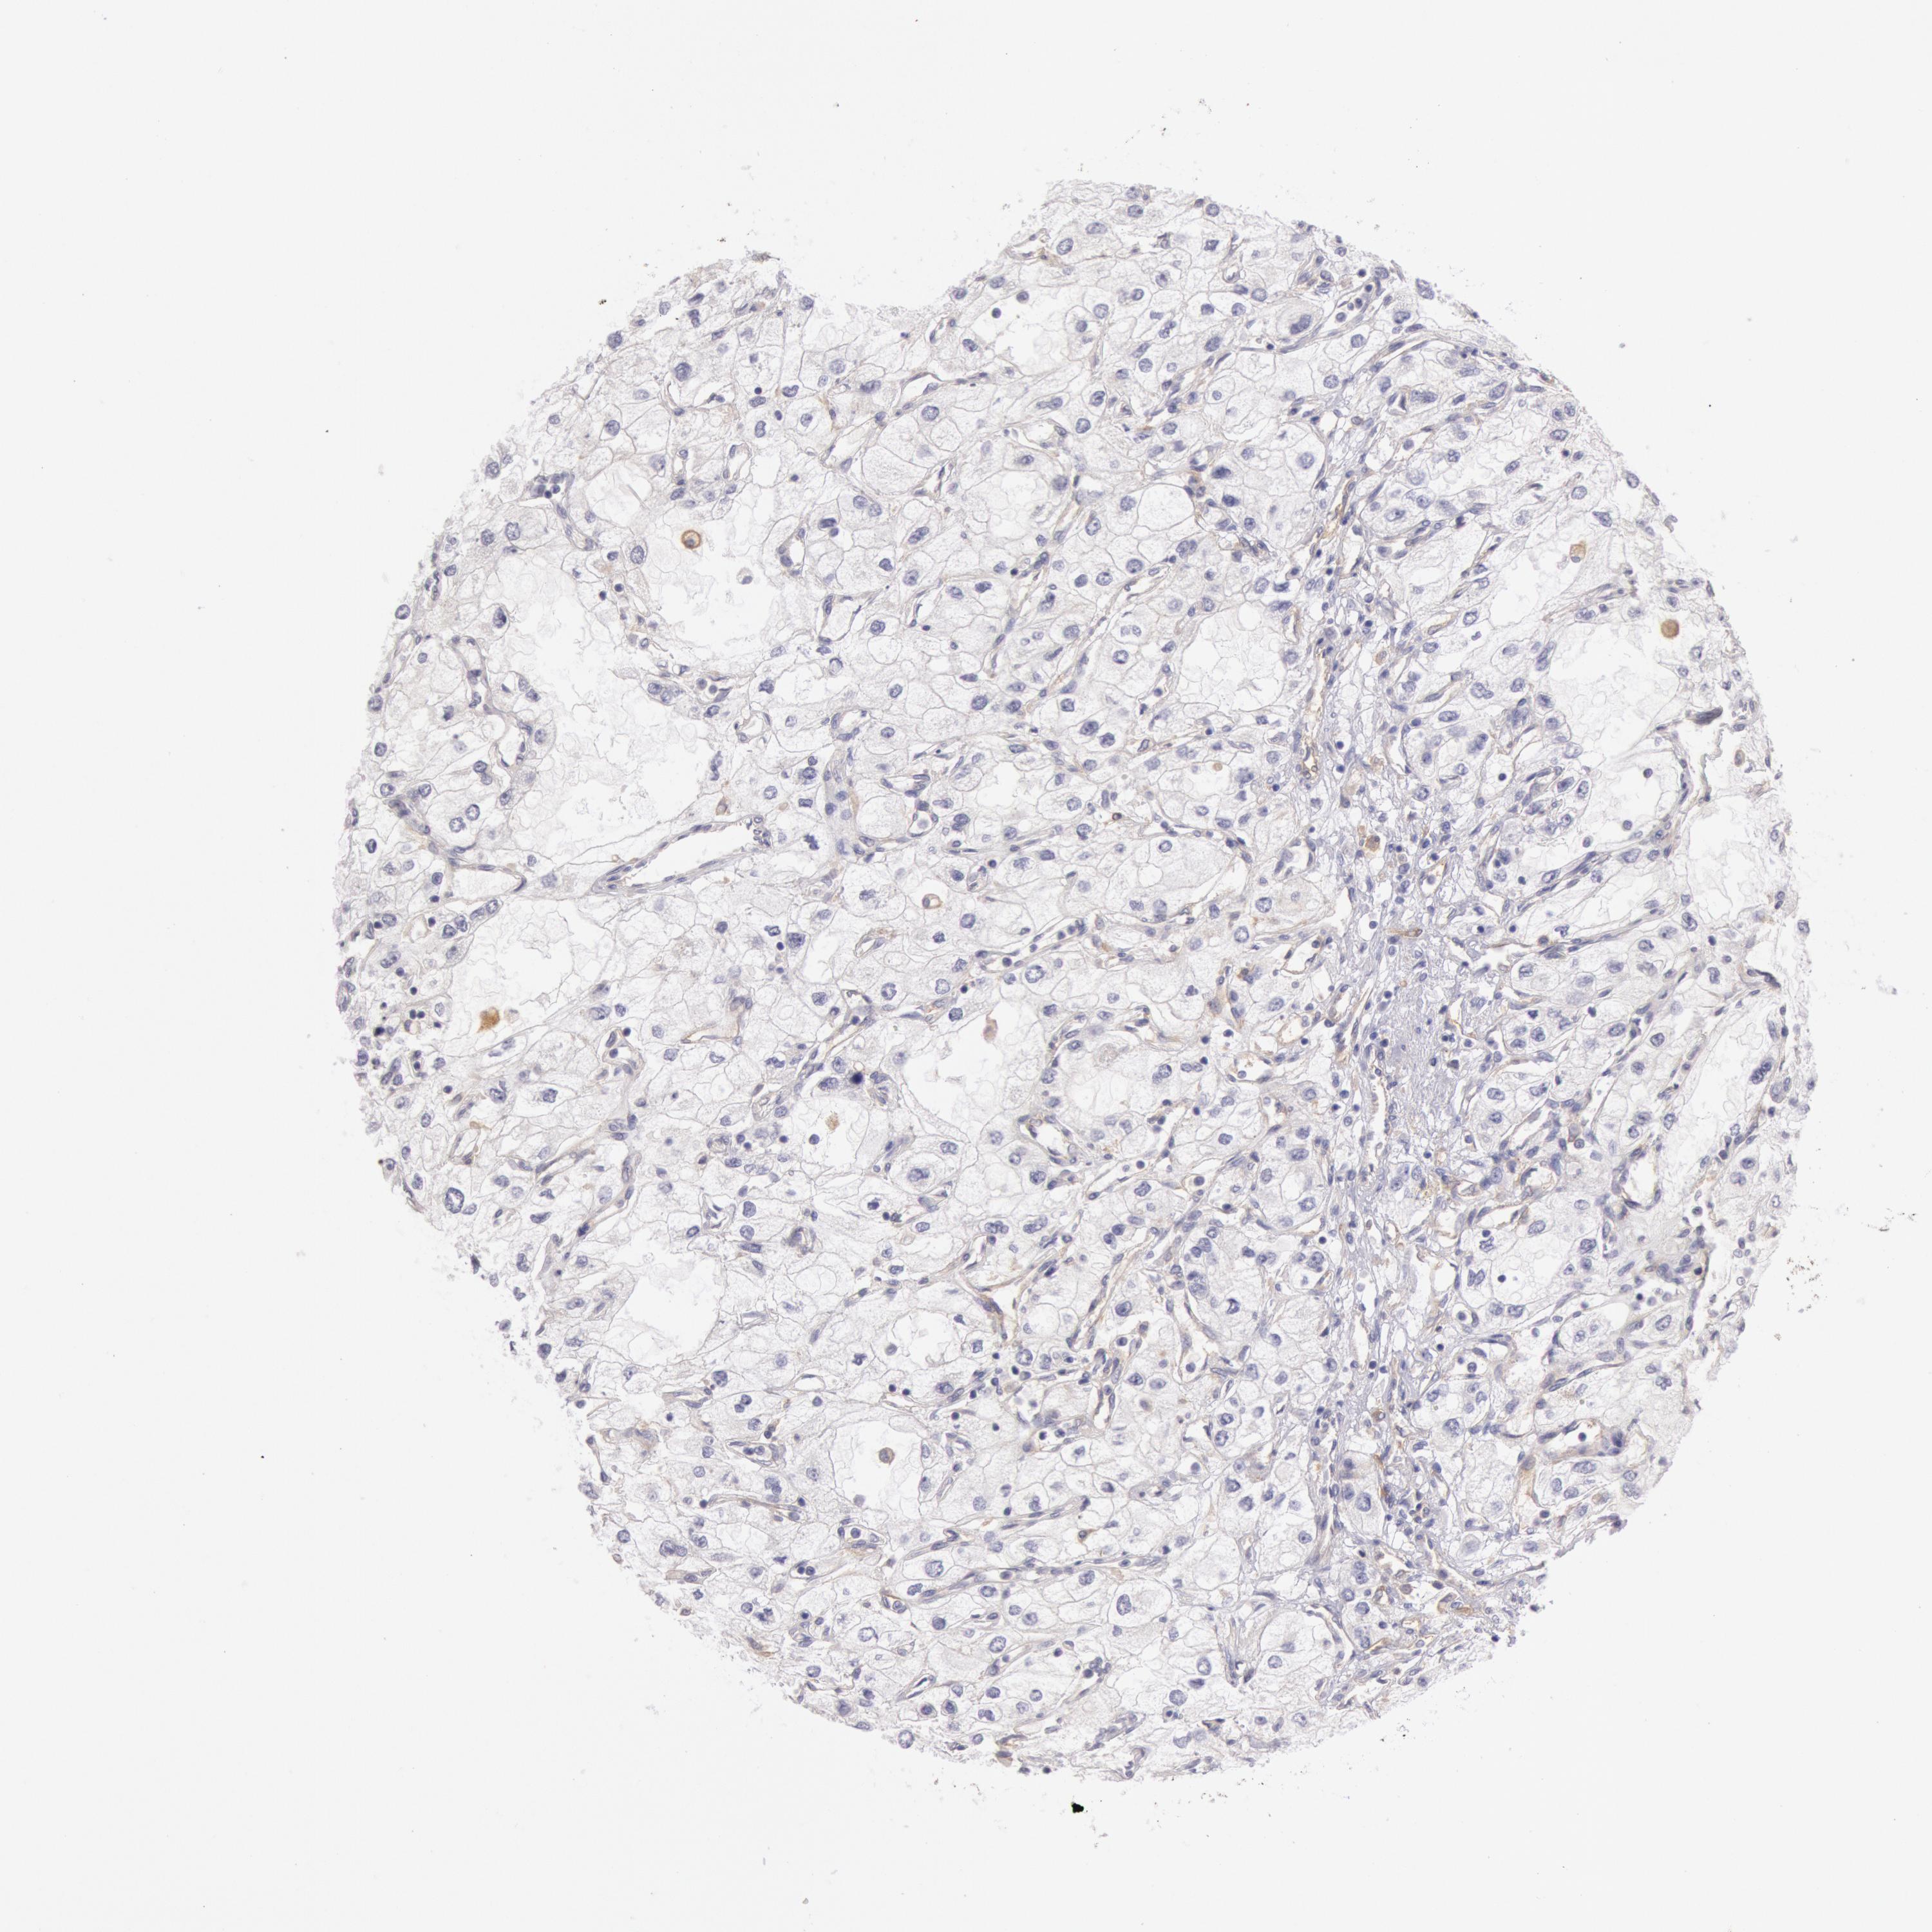

KIDNEY RENAL CLEAR CELL CARCINOMA (TCGA) - Interactive survival scatter ploti

The Survival Scatter plot shows the clinical status (i.e. dead or alive) for all individuals in the patient cohort, based on the same data that underlies the corresponding Kaplan-Meier plots. Patients that are alive at last time for follow-up are shown in blue and patients who have died during the study are shown in red.

The x-axis shows the expression levels (FPKM) of the investigated gene in the tumor tissue at the time of diagnosis. The y-axis shows the follow-up time after diagnosis (years). Both axes are complimented with kernel density curves demonstrating the data density over the axes. The top density plot shows the expression levels (FPKM) distribution among dead (red) and alive patients (blue). The right density plot shows the data density of the survived years of dead patients with high and low expression levels respectively, stratified using the cutoff indicated by the vertical dashed line through the Survival Scatter plot. This cutoff is automatically defined based on the FPKM cutoff that minimizes the p-score. The cutoff can be changed by dragging the vertical line or by entering a cutoff value in the square labeled "Current cut-off".

Under the Survival Scatter plot the p-score landscape (black curve; left axis) is shown together with dead median separation (red curve; right axis). Dead median separation is the difference in median mRNA expression between patients who have died with high and low expression, respectively. It is calculated as follows: median FPKM expression of dead patients with high expression - median FPKM expression of dead patients with low expression. This is intended to aid the user in visually exploring custom cutoffs and the associated p-scores and dead median separation.

Individual patient data is displayed and can be filtered by clicking on one or more of the category buttons on the top of the page. Categories describing expression level and patient information include: high, low, alive, dead, female, male and tumor stages. The scale of the x-axis can be toggled between linear and log-scale by clicking on the "x log" button. Mouse-over function shows TCGA ID, patient information and mRNA expression (FPKM) for each patient.

& Survival analysisi

Kaplan-Meier plots summarize results from analysis of correlation between mRNA expression level and patient survival. Patients were divided based on level of expression into one of the two groups "low" (under cut off) or "high" (over cut off). X-axis shows time for survival (years) and y-axis shows the probability of survival, where 1.0 corresponds to 100 percent.

MYO5A is potential prognostic, high expression is favorable in Kidney Renal Clear Cell Carcinoma (TCGA)

: 9.47

Average pTPM 7.6

Number of samples 521